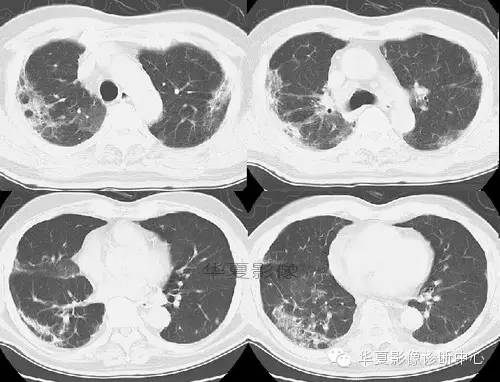

【病例】慢性嗜酸细胞性肺炎1例CT影像表现

患者,女,50岁。干咳、进行性呼吸困难、发热和体重减轻。

CT图像特点:双侧胸膜下片状、蜂窝状改变,肺内长条索状影向胸膜延伸。

结果:慢性嗜酸细胞性肺炎

点评:本病是寄生虫(钩虫、蛔虫等)和药物(呋喃妥因等)所致的变态反应,为肺部嗜酸粒细胞浸润的一种消耗性疾病。 慢性嗜酸粒细胞性肺炎:患者多见于中青年女性,发热、体重减轻、盗汗。咳嗽多粘痰,伴气急和咯血。周围血嗜酸粒细胞比例多在20%-70%。肺间质、肺泡和细支气管内有白细胞浸润,主要为成熟嗜酸粒细胞,少量组织细胞和淋巴细胞,肺泡中可见细胞内含有嗜酸性颗粒和尖棱结晶的多核巨细胞,此为本病的病理特点。有些肺小血管,主要是肺静脉有血管炎,有时见多核巨细胞及嗜酸肉芽肿。

胸部X片显示不呈段或叶性分布的周围片状阴影,常为双侧分布。糖皮质激素治疗后48h内症状和胸片可迅速消失。在同一局部可反复发生,数年后变为纤维化或蜂窝状改变。 糖皮质激素治疗效果显著,常可恢复正常,因停药较易复发,故全疗程需在一年以上。